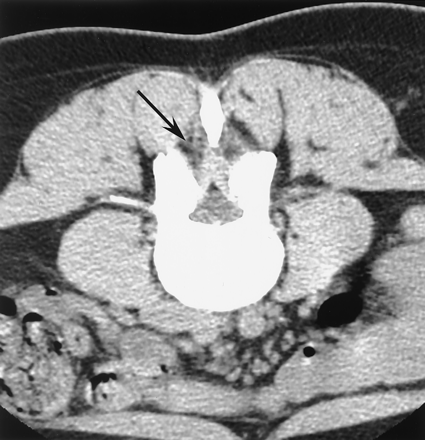

Lateral fluoroscopic images of a 52-year-old man with back pain and leg pain during LESI procedure.

A, Contrast medium injected at loss of resistance is seen overlying the deep paraspinal region just posterior to the ligamentum flavum and spinal canal (arrows).

B, The needle was advanced and the epidural space is correctly engaged and the correct needle-tip location is confirmed with epidurogram (white arrow). Initial injection is also visible (black arrowhead).